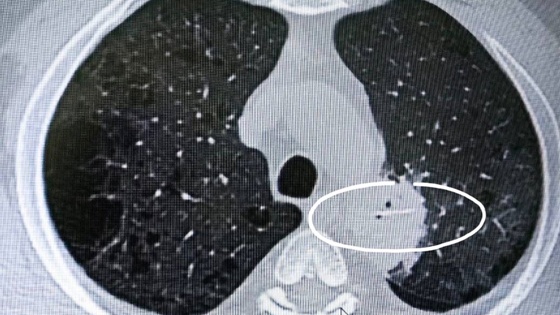

62-летний югорчанин почти сразу после трапезы почувствовал дискомфорт в области пищевода и боль при глотании, но к врачу пошел только через три дня, когда поднялась температура. На КТ было видно инородное тело в средостении - это пространство между правым и левым плевральными мешками (то есть кость проткнула пищевод и мигрировала в грудную полость).

На момент госпитализации инородное тело уже находилось в левом легком, начался абсцесс.